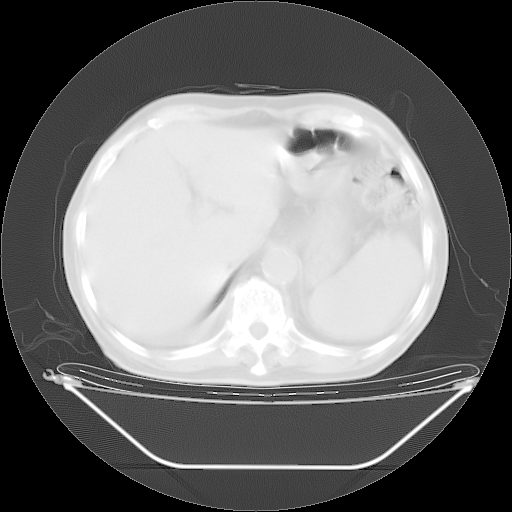

今天复查肺部CT,发现双肺广泛磨玻璃样改变。所以我把3月19日和5月9日相隔50天的肺部CT上传。请大家会诊。

2009年3月19日肺部CT片。

2009年3月19日肺部CT

5月9日肺部CT(在4月27日齐鲁医院肺部CT描述部分肺组织磨玻璃样改变,12天后肺组织广泛磨玻璃样改变)

大致读了系列胸部CT:纵隔窗无明显异常,肺窗:从4、27至今:主要是双肺中下野外带可见毛玻璃样改变,目前处于急性肺泡炎阶段,至于原因考虑1、结替组织或胶原血管性疾病所致?2、恶性疾病如恶组在肺部所致的表现或细支气管肺泡癌?3、药物或其它原因如肺蛋白沉着症所致肺泡炎目前不太可能?总之,明天就去请我院的呼吸科、感染科、血液科和临免专家会诊哈。